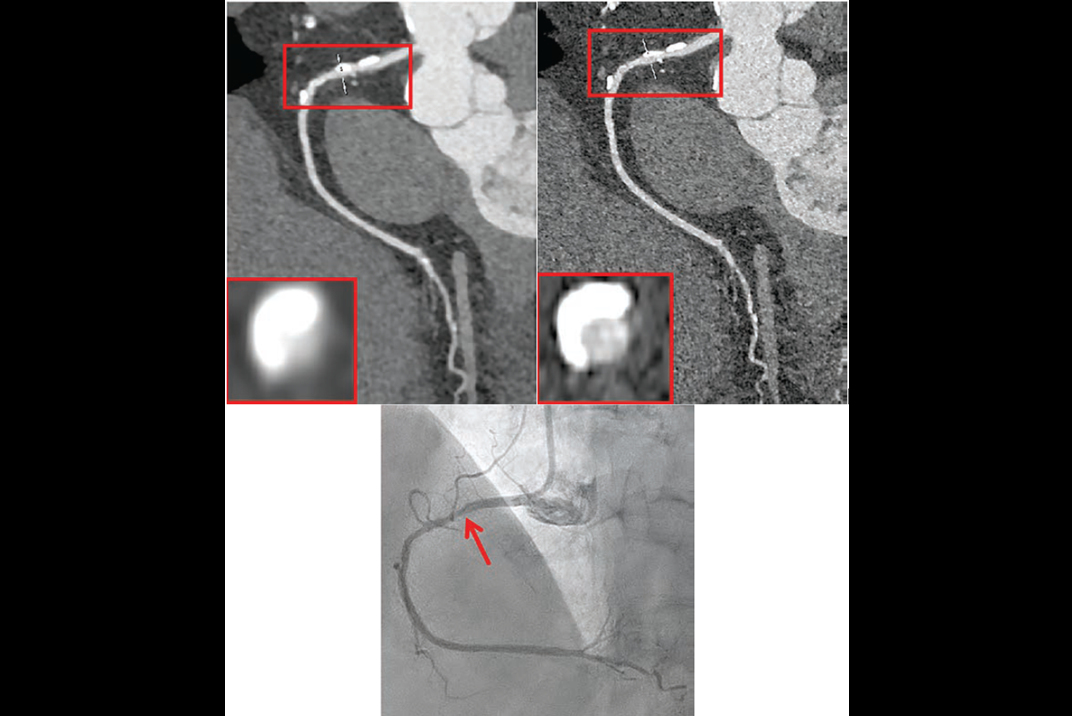

"We had a policy that you had to convince the group," he said, noting examples where the group saw evidence that diagnostic imaging using PCCT improved patient management and outcome in cases involving temporal bone imaging (highlighting an eroding ossicular implant), and pediatric cystic fibrosis.

"Those are both diagnoses that were only able to be made on this scanner that could not be made when the patient was scanned on the conventional force scanner," Froemming said, noting "huge dose reduction potential, and much more actionable clinical information."

Temporal bone imaging using photon counting CT illuminated the ossicular implant.Adam Froemming, MD, Mayo Clinic, via ISCT.